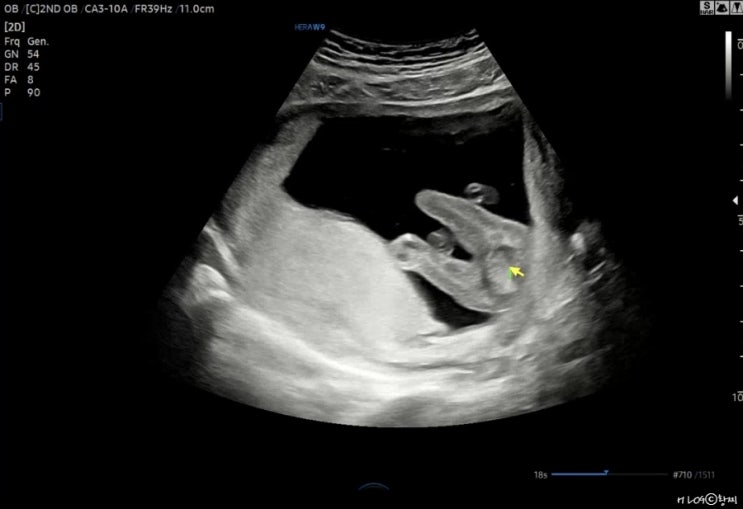

[임신 20주] 정밀초음파 검사

시간 왜케 빨라 내가 6갤이라뇨 갑분벚꽃 갑자기 날씨가 따뜻해지면서 핀 벚꽃 넘 이쀼리 임신한 친구네 부...